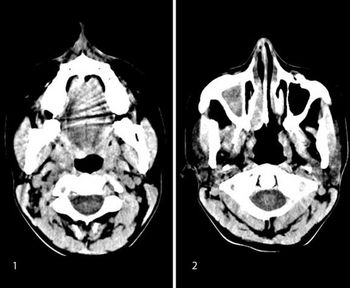

A 73-year-old male with history of a lung mass on recent chest radiograph presents with headaches.